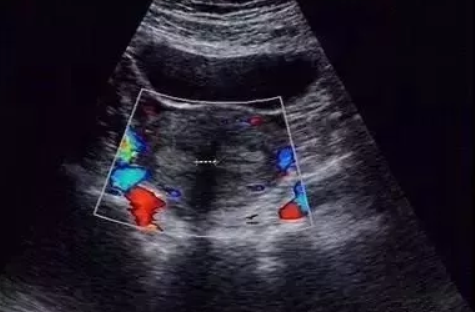

縱膈子宮外形正常,但宮底橫徑較寬;宮底水平橫切面顯示子宮內(nèi)部縱隔,其兩側(cè)各見一宮內(nèi)膜回聲;三維超聲子宮冠狀切面成像顯示不完全縱隔子宮為Y形。